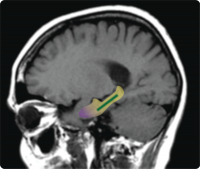

Hippocampal region

Dentate gyrus

The dentate gyrus is distinct from the entorhinal cortex, the hippocampal region affected in early-stage Alzheimer’s disease. Previous work, including by the laboratory of senior author Scott A. Small, MD, had shown that changes in a specific part of the brain’s hippocampus—the dentate gyrus—are associated with normal age-related memory decline in humans and other mammals. Credit: Columbia University Medical Center